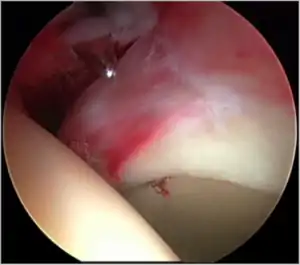

Figure 7. A complex labral tear. An arthroscopic probe is seen at the junction of the labrum and acetabular rim

Labral tears (see fig. 7)

The acetabular labrum is a fibrous structure, which surrounds the femoral head. It forms a seal to the hip joint,[15] although its true function is poorly understood. Recent evidence has demonstrated that this hydraulic seal is vital for maintaining stability of the ball and socket joint [16] and reducing contact pressures of the femur to the acetabulum.[17] The labrum has also been shown to have a nerve supply and as such may cause pain if damaged.[18] The underside of the labrum is continuous with the acetabular articular cartilage so any compressive forces that affect the labrum may also cause articular cartilage damage, particularly at the junction between the two, the chondrolabral junction. The labrum may be damaged or torn as part of an underlying process, such as FAI or dysplasia (shallow hip socket), or may be injured directly by a traumatic event. Depending on the type of tear, the labrum may be either trimmed (debrided) or repaired. Removing or debriding the labrum is becoming less popular as the latest research shows that results are more predictable in the long term if the labrum can be repaired. Various techniques are available for labral repair, mainly using anchors, which may be used to re-stabilise the labrum against the underlying bone, allowing it to heal in position.

New techniques are prevalent in hip arthroscopy. There is good evidence to support the creation of a new labrum by performing a labral reconstruction if the patient has previously had a labral debridement, has an ossified labrum, or the current labrum is too small or injured for a repair.[16] Labral reconstruction involves creating a new labrum either from the patients own tissue (autograft) or from cadaver tissue (allograft). The new labrum is then anchored into position with bone anchors and the hip then goes through extensive rehab.